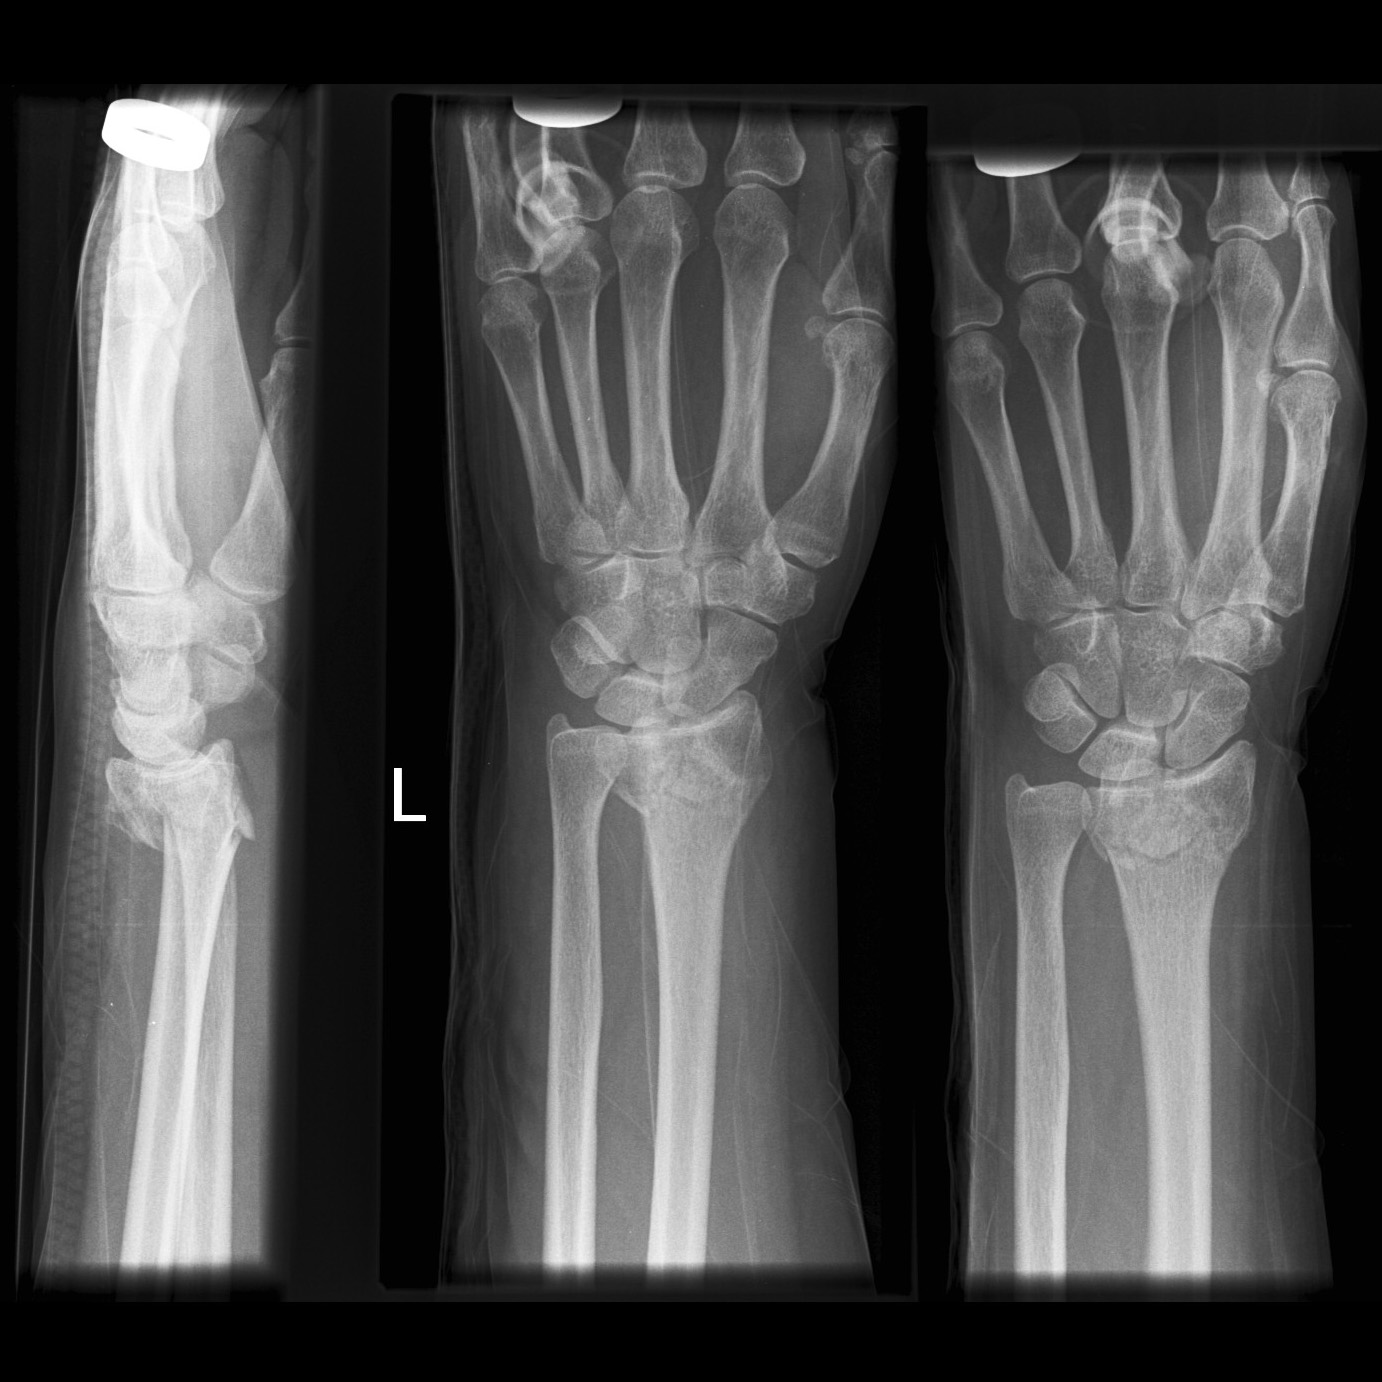

Colles' Fracture

This type of fracture is often described as being an extra-articular transverse fracture of the distal radius with dorsal displacement with/without ulnar styloid fracture. The fracture is usually around 2cm proximal to the radiocarpal joint.

1. X-Ray: AP and Later x-rays of the wrist. Oblique views of the wrist may also be beneficial. The radiological features include:

1. Dorsal tilt of the distal fragment

2. Dorsal displacement of the distal fragment

3. Ulnar styloid fracture

4. Radial shortening

5. Radial tilt

6. Radial displacement

Case courtesy of Assoc Prof Frank Gaillard, Radiopaedia.org. From the case rID: 12382